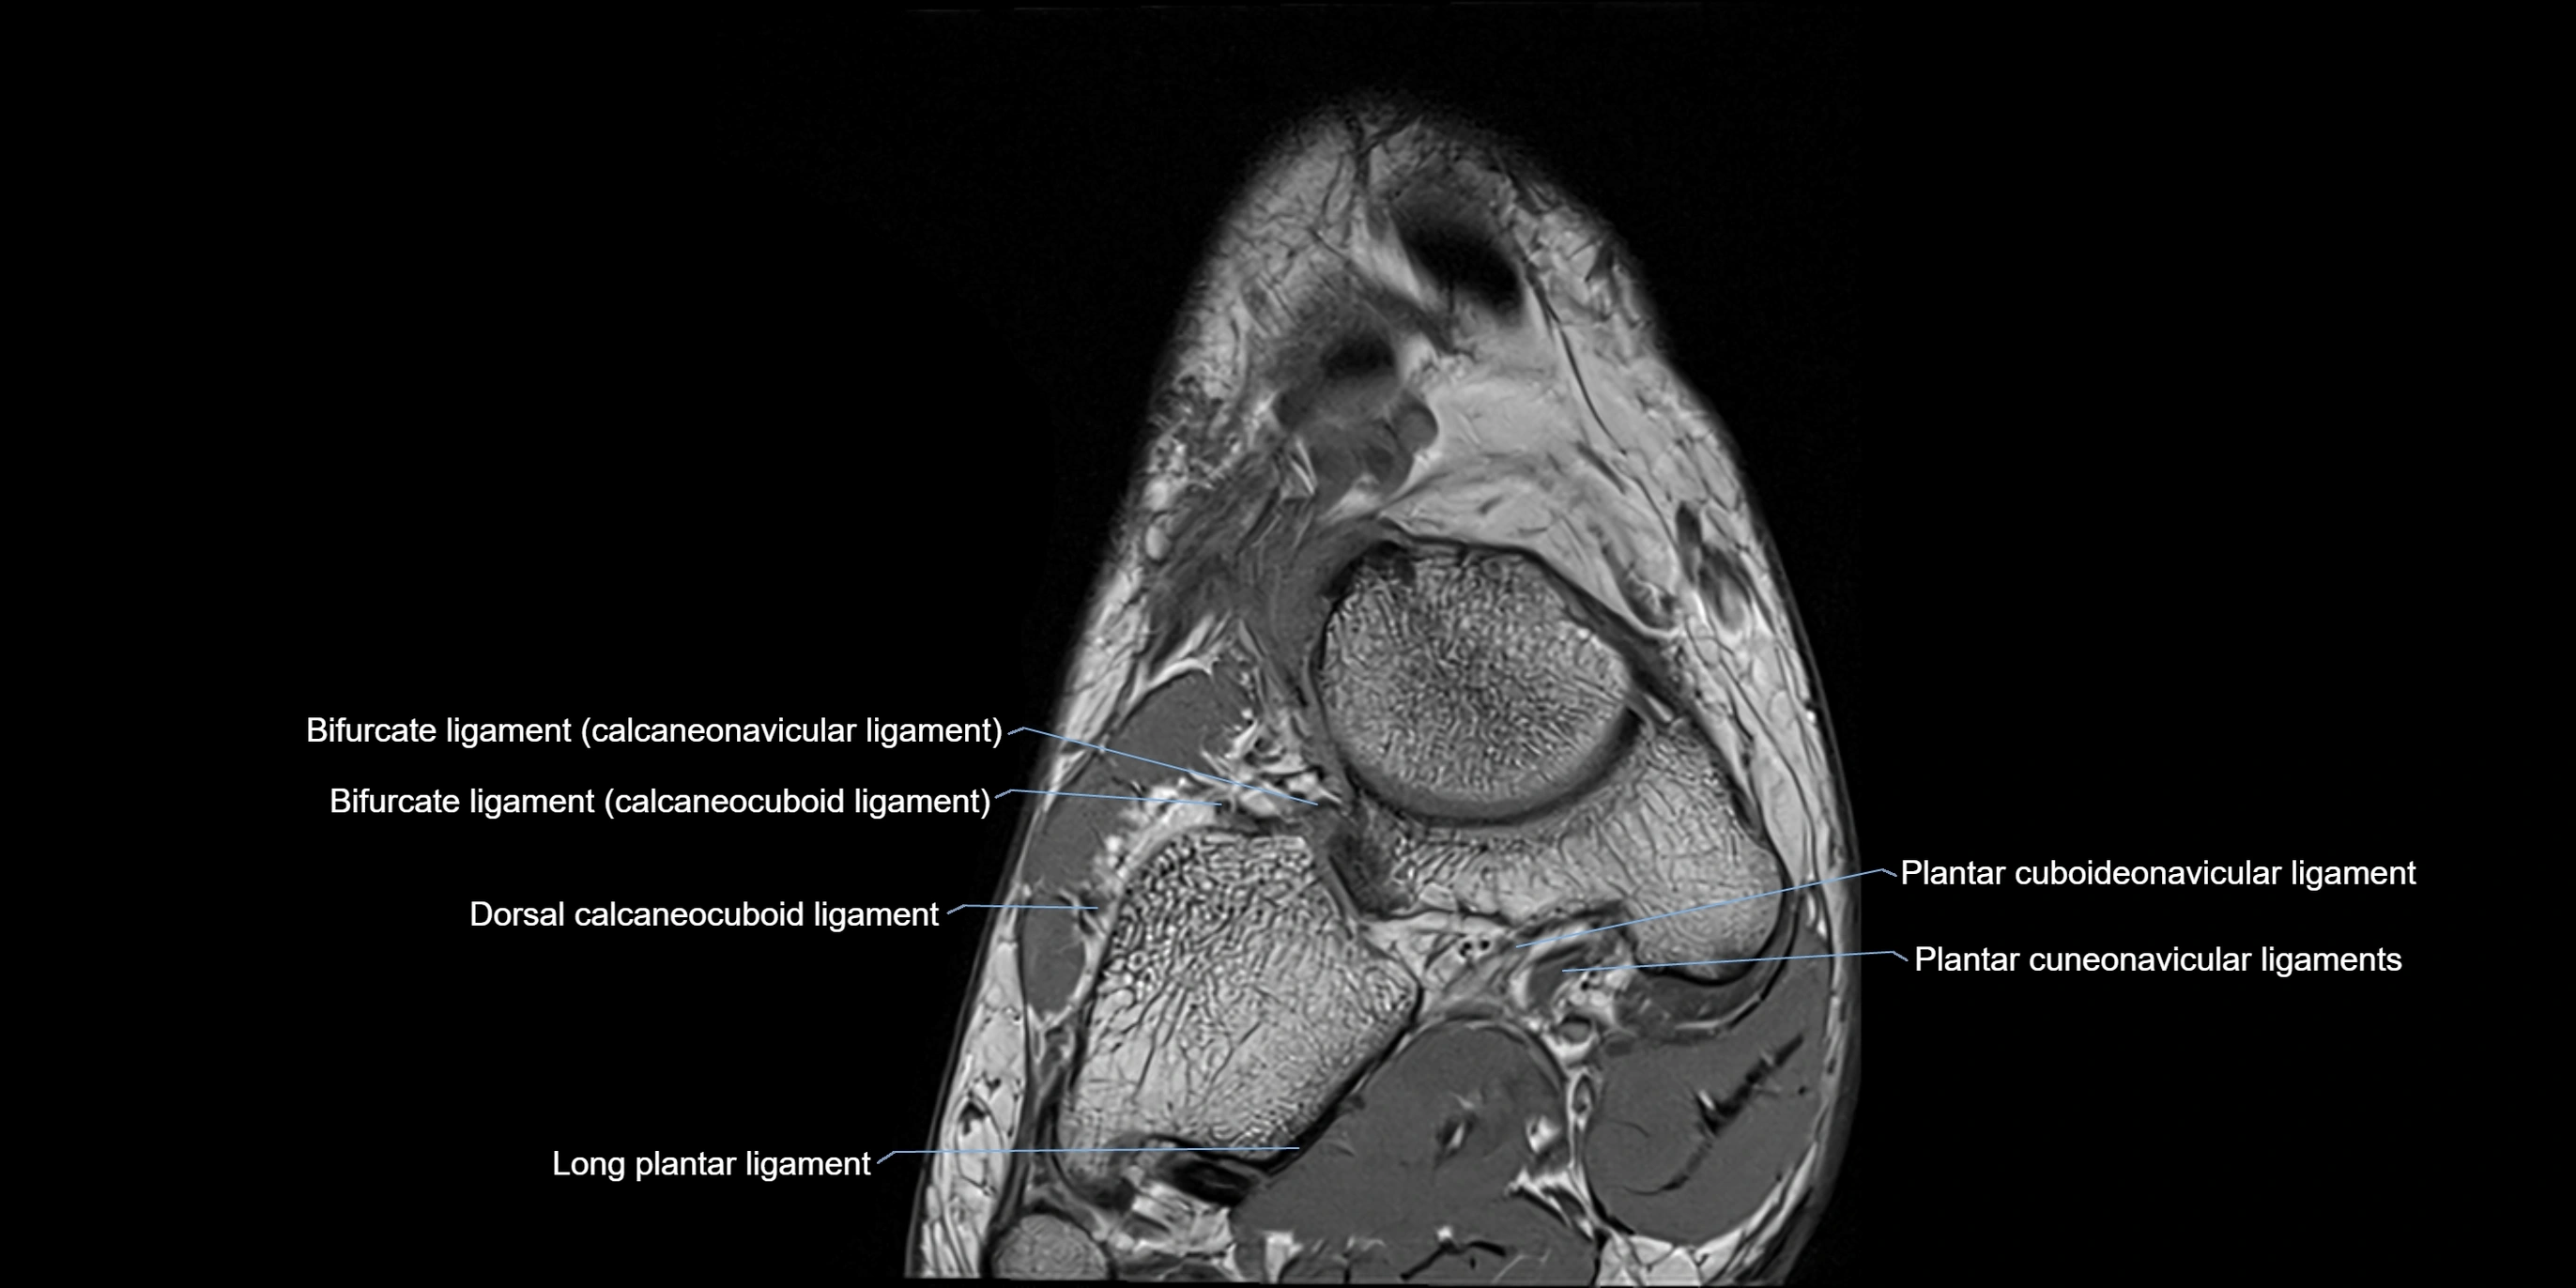

MRI image

image